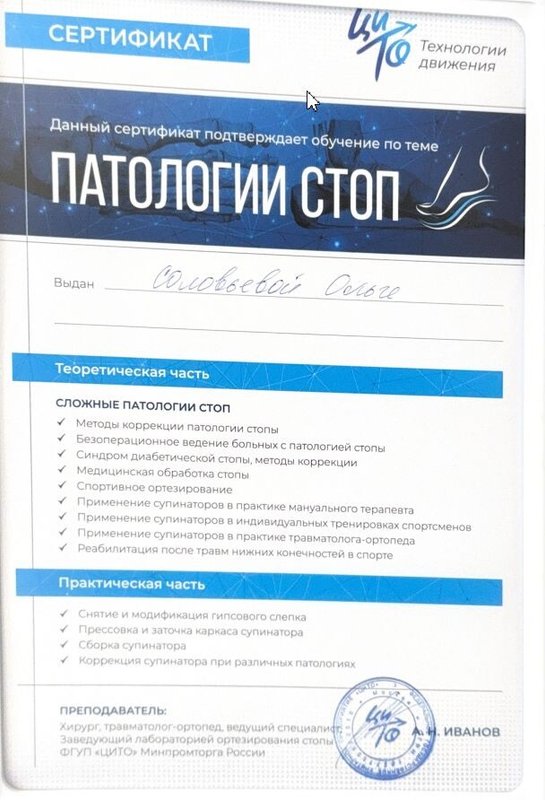

Знаю Ольгу Игоревну давно и уверена в ее профессионализме. Она постоянно учится и помогала мне с проблемами рук и ног, всегда справлялась сама, никого не перенаправляла. Она талантливый и умный доктор, профессионал.